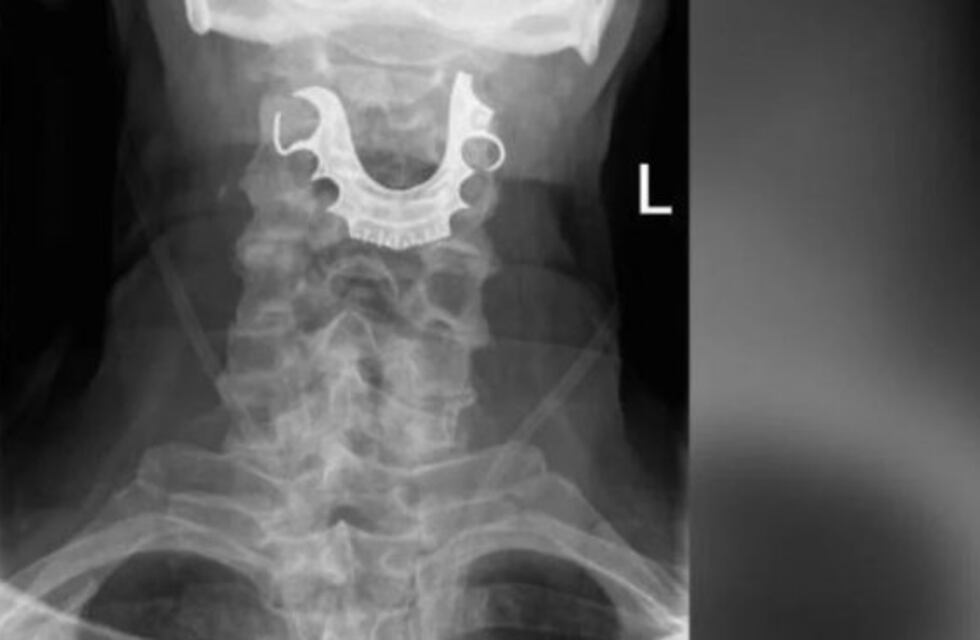

Finalmente, los rayos x encontraron el verdadero problema: una dentadura postiza sobre las cuerdas vocales del hombre. El sujeto dijo que había perdido los dientes durante su visita inicial al hospital, y finalmente debió ser sometido a una nueva intervención para extraerlos.